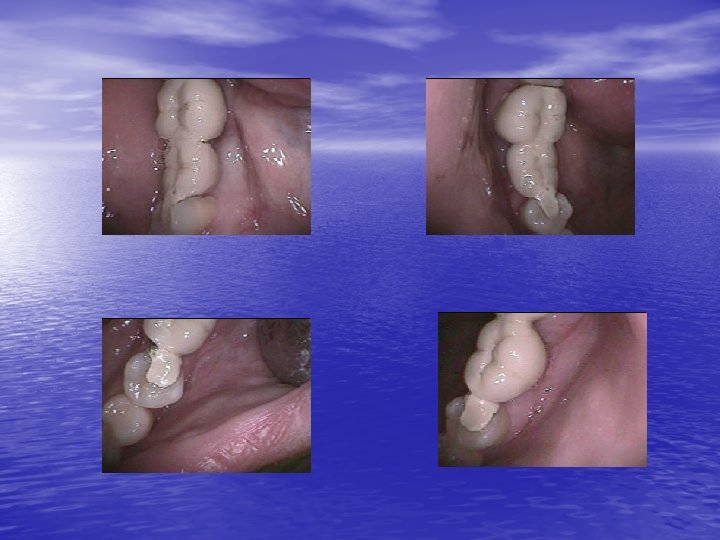

Second clinical case